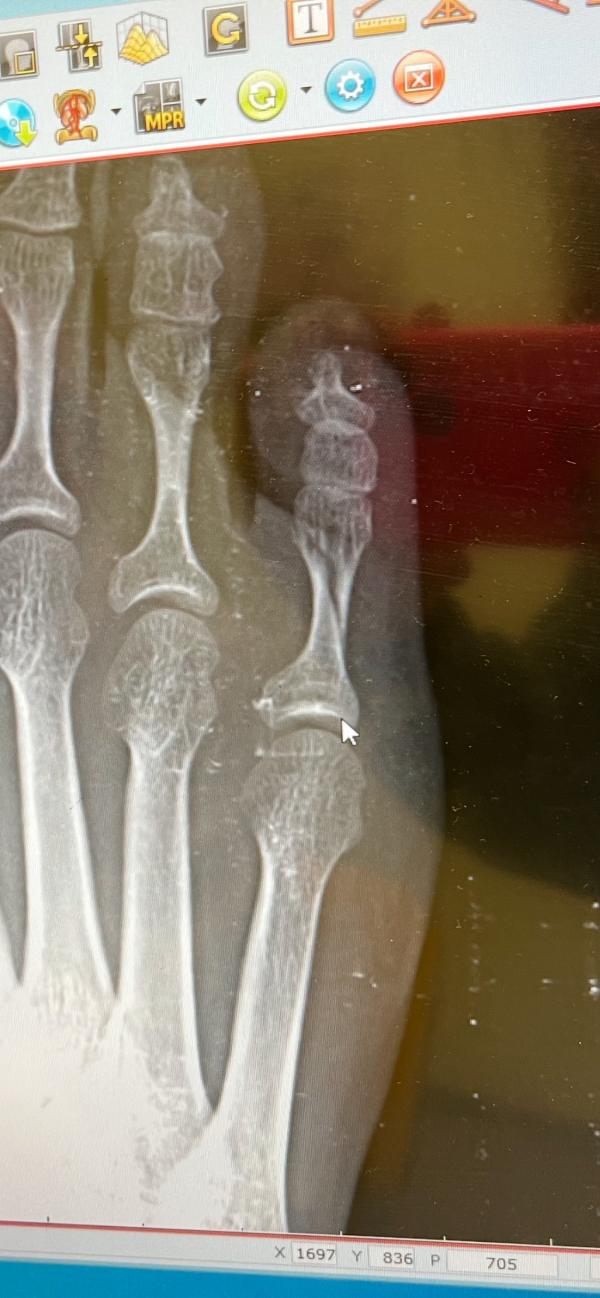

Когда встреча ножки дивана и мизинца оказалась фатальной😃

Привет,перелом